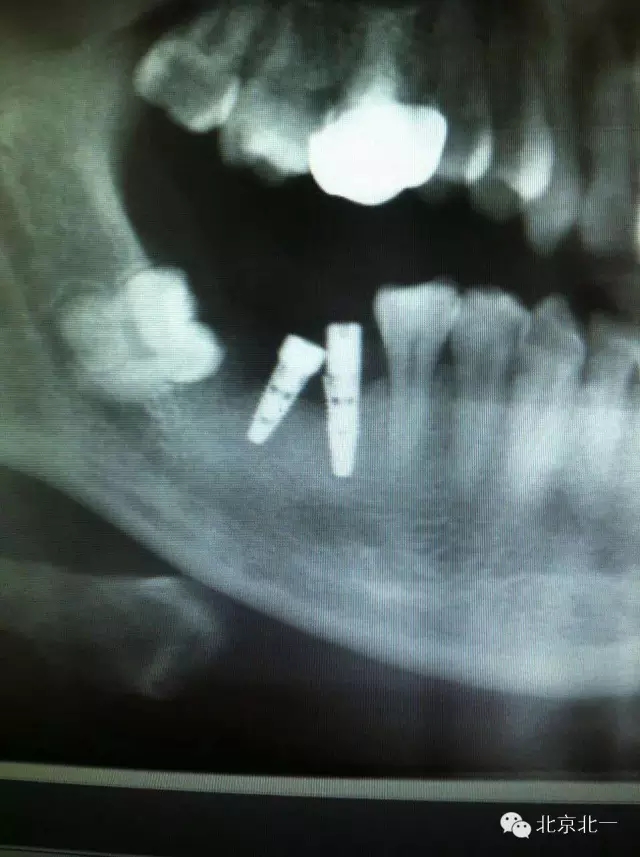

附圖:種植體植入角度不佳導致愈合基臺無法就位,如果在前牙區(qū)可能帶來美學更大問題。值得思考。